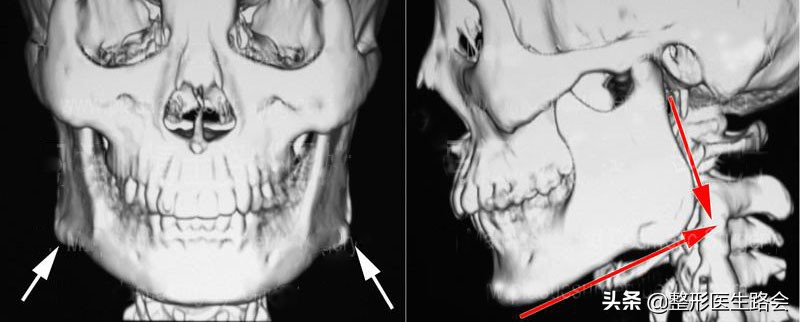

下颌角外翻、肥大

前些天门诊来了一位“国字脸”的求美者,想改脸型的需求特别迫切,面诊之后发现她的下颌角比较肥大,而且有呈直角的趋势,需要通过下颌角手术来矫正。

为了术后正面看起来更自然一些,因此还需要结合皮质骨切除术。